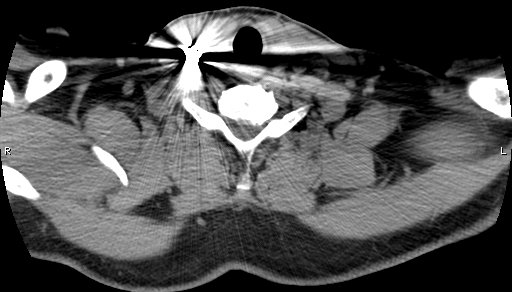

CT Neck showed metallic foreign body piercing the right sternocleidomastoid muscle at the level of lower border of C6 vertebral body, likely abutting the carotid sheath at the level of lower border of cricoid cartilage on right side of neck. Soft tissue density anterior to IJV and CCA -likely haematoma